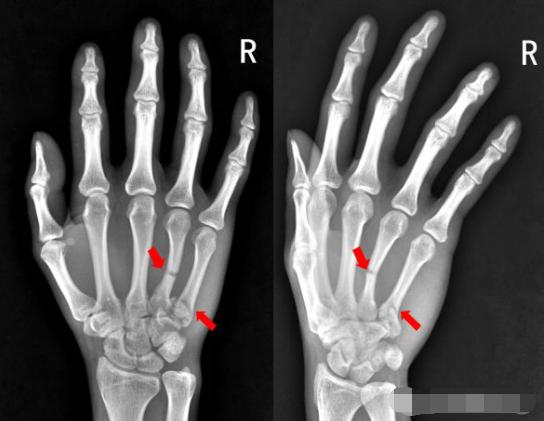

6、患者右手被车门挤压,拍片如下:

右手第四掌骨中段、第五掌骨基底部见横行骨折透亮线,骨折端对位对线尚可,第四、第五掌骨骨折。